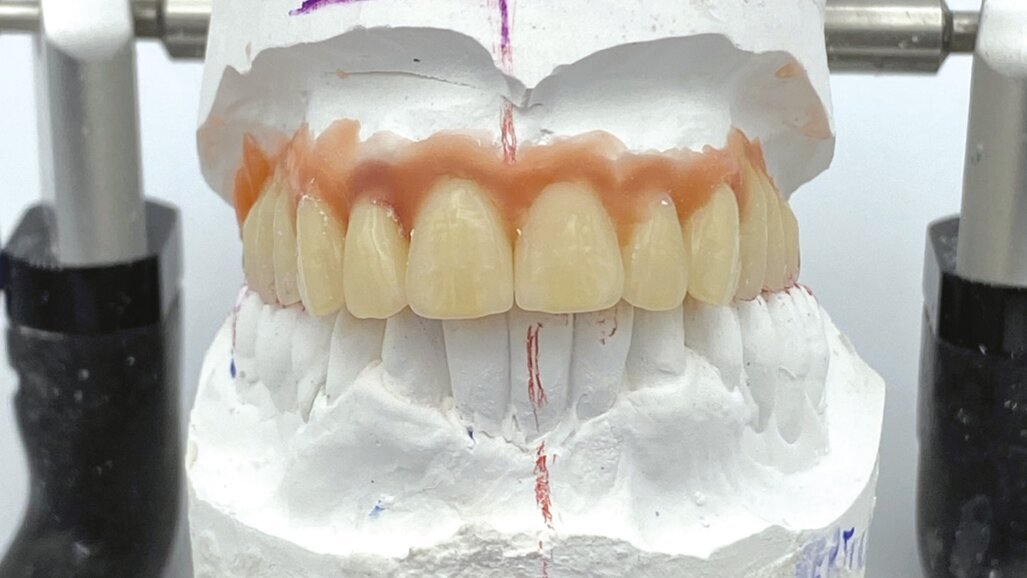

Nel laboratorio odontotecnico vengono messi in articolatore i modelli iniziali e si esegue uno studio del caso con Digital Smile Design e della situazione occlusale, per valutare eventuali rialzi della dimensione verticale e le correzioni estetiche. Le informazioni così ottenute vengono riportate nella ceratura diagnostica che in questo caso è un montaggio diagnostico/definitivo (Fig. 3). Definitivo in quanto si utilizzano già i denti del lavoro finale per il montaggio diagnostico, che vengono sfruttati per realizzare due protesi identiche in resina (Fig. 4). La prima verrà consegnata alla paziente immediatamente dopo aver inserito gli impianti. La seconda diventerà una dima protesica per la realizzazione della protesi definitiva, che verrà applicata a 7 giorni dall’intervento chirurgico.

Fig. 3 - Montaggio diagnostico.

Fig. 4 - Due protesi in resina bianca: una diventerà il provvisorio immediato per il paziente, l’altra la dima protesica.